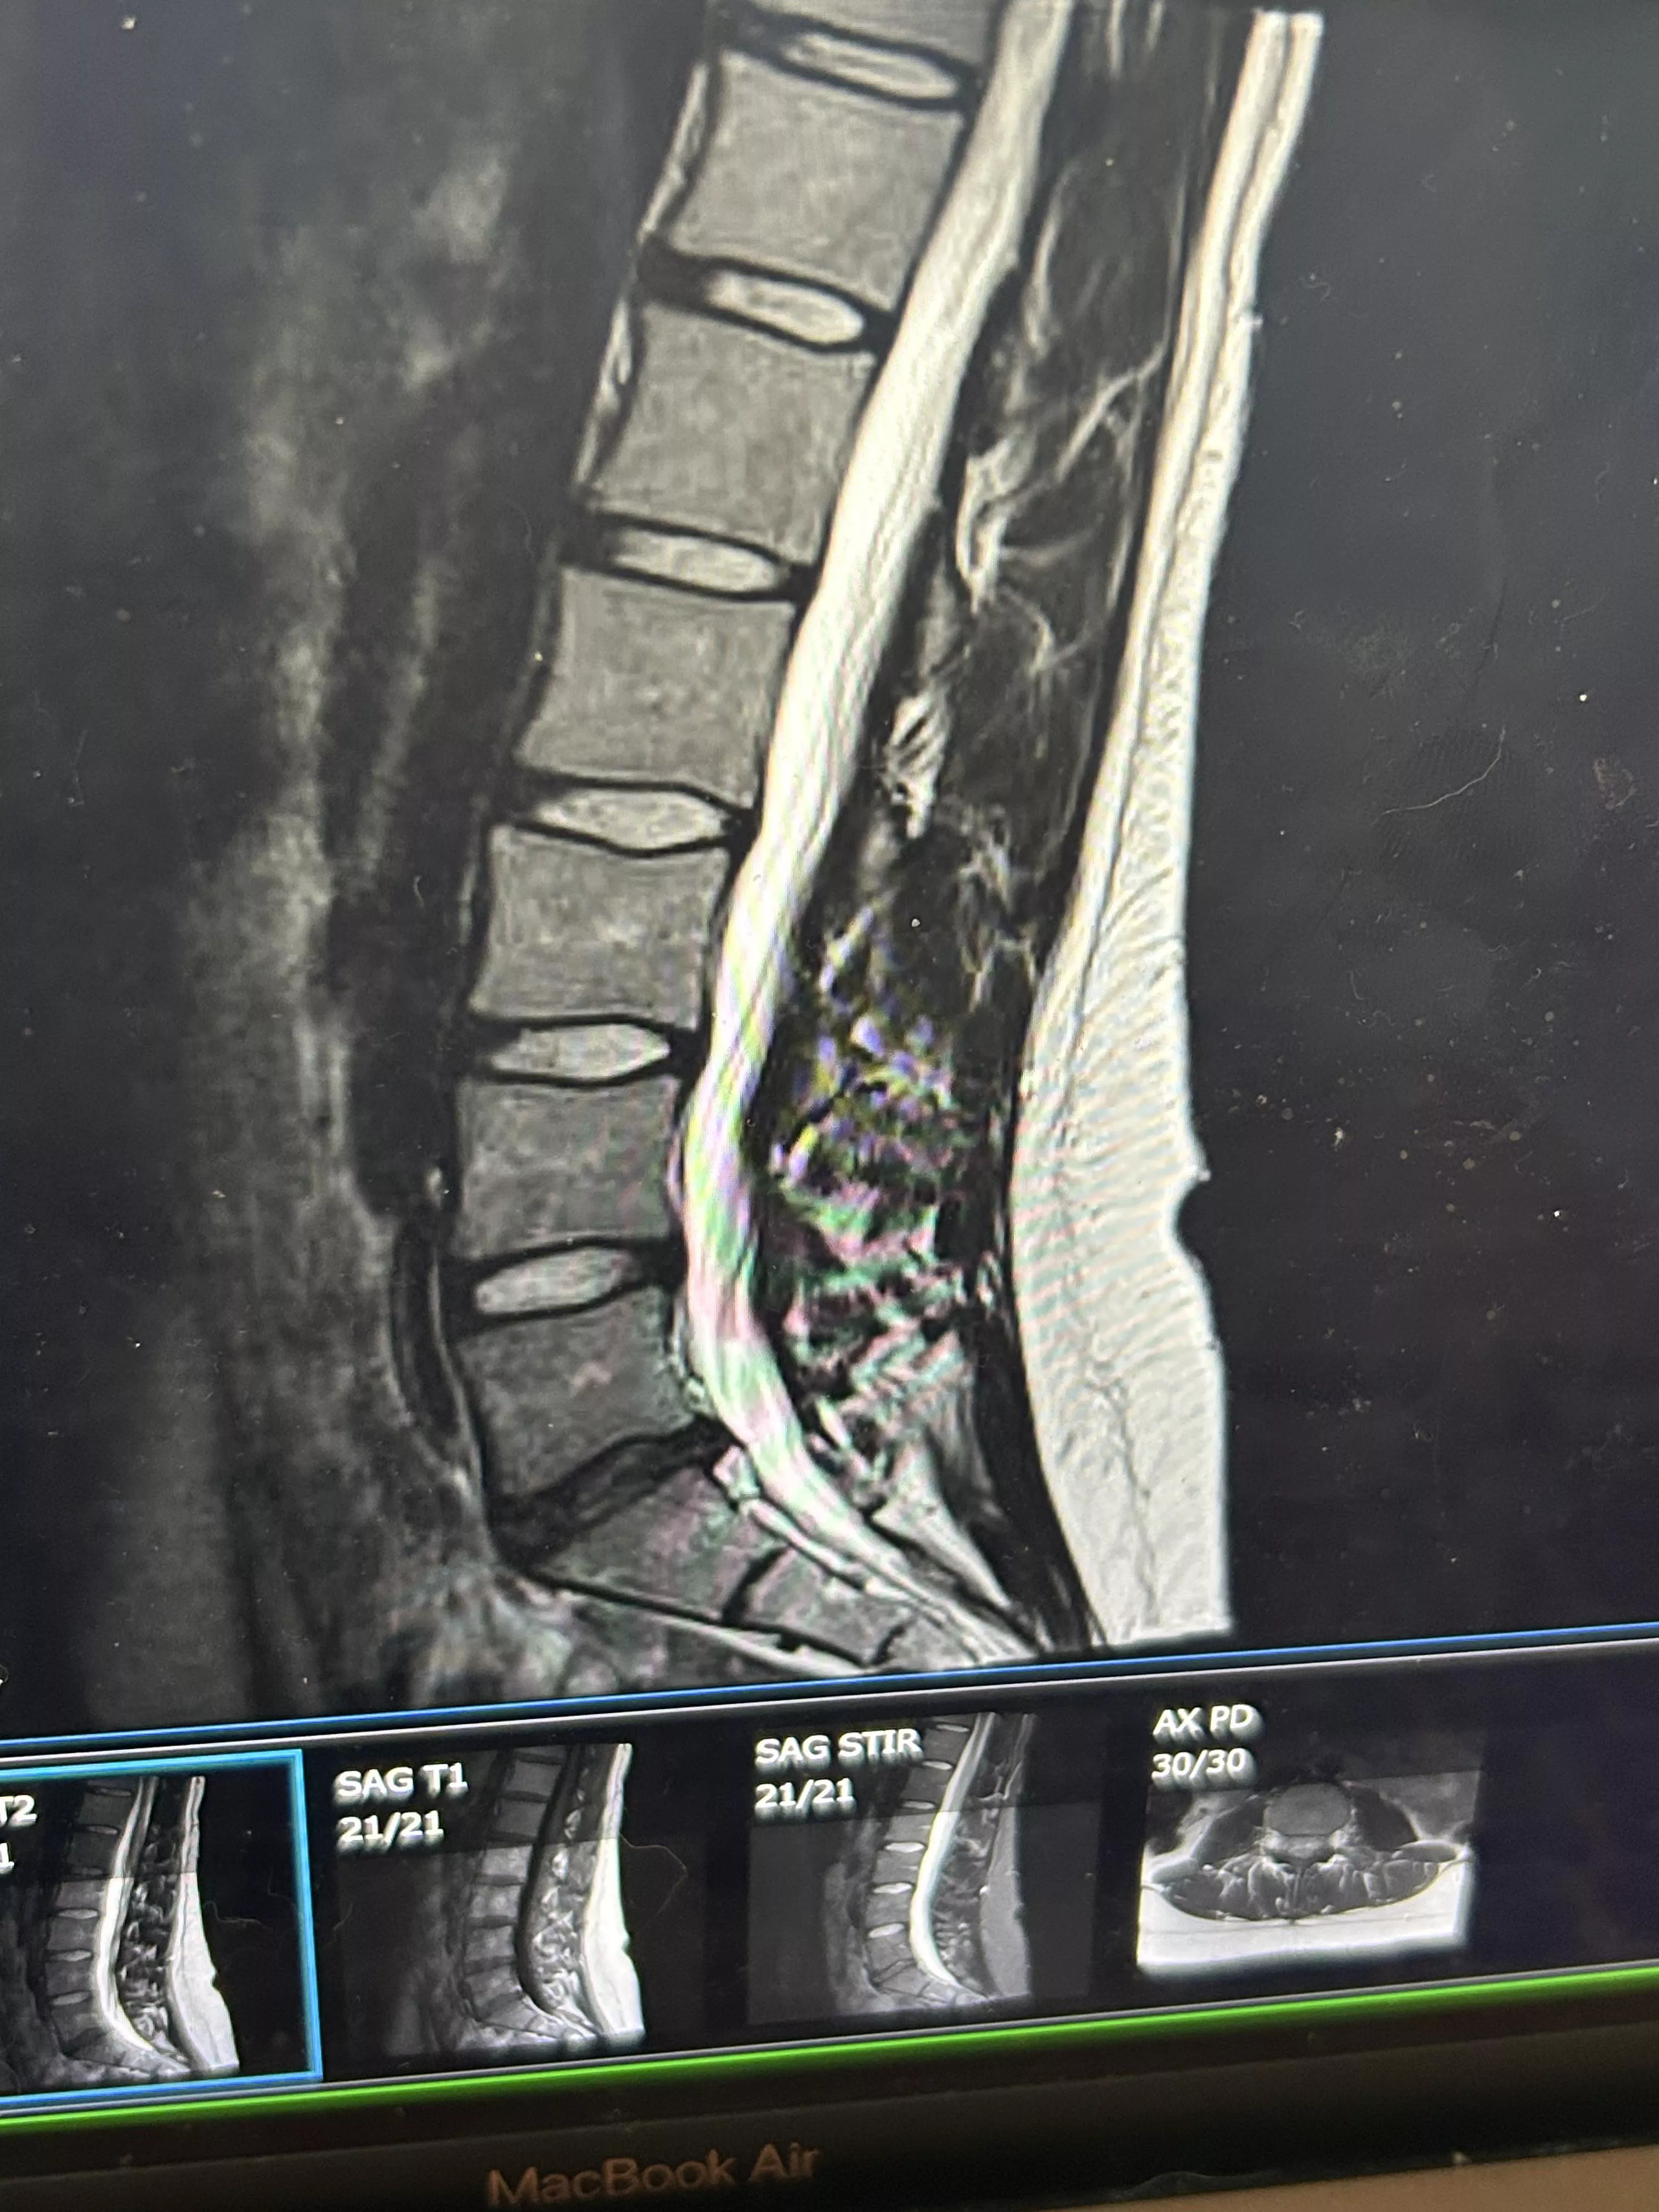

Is this bulging disc enough to cause significant pain and get a PT script nudes

Category: medical